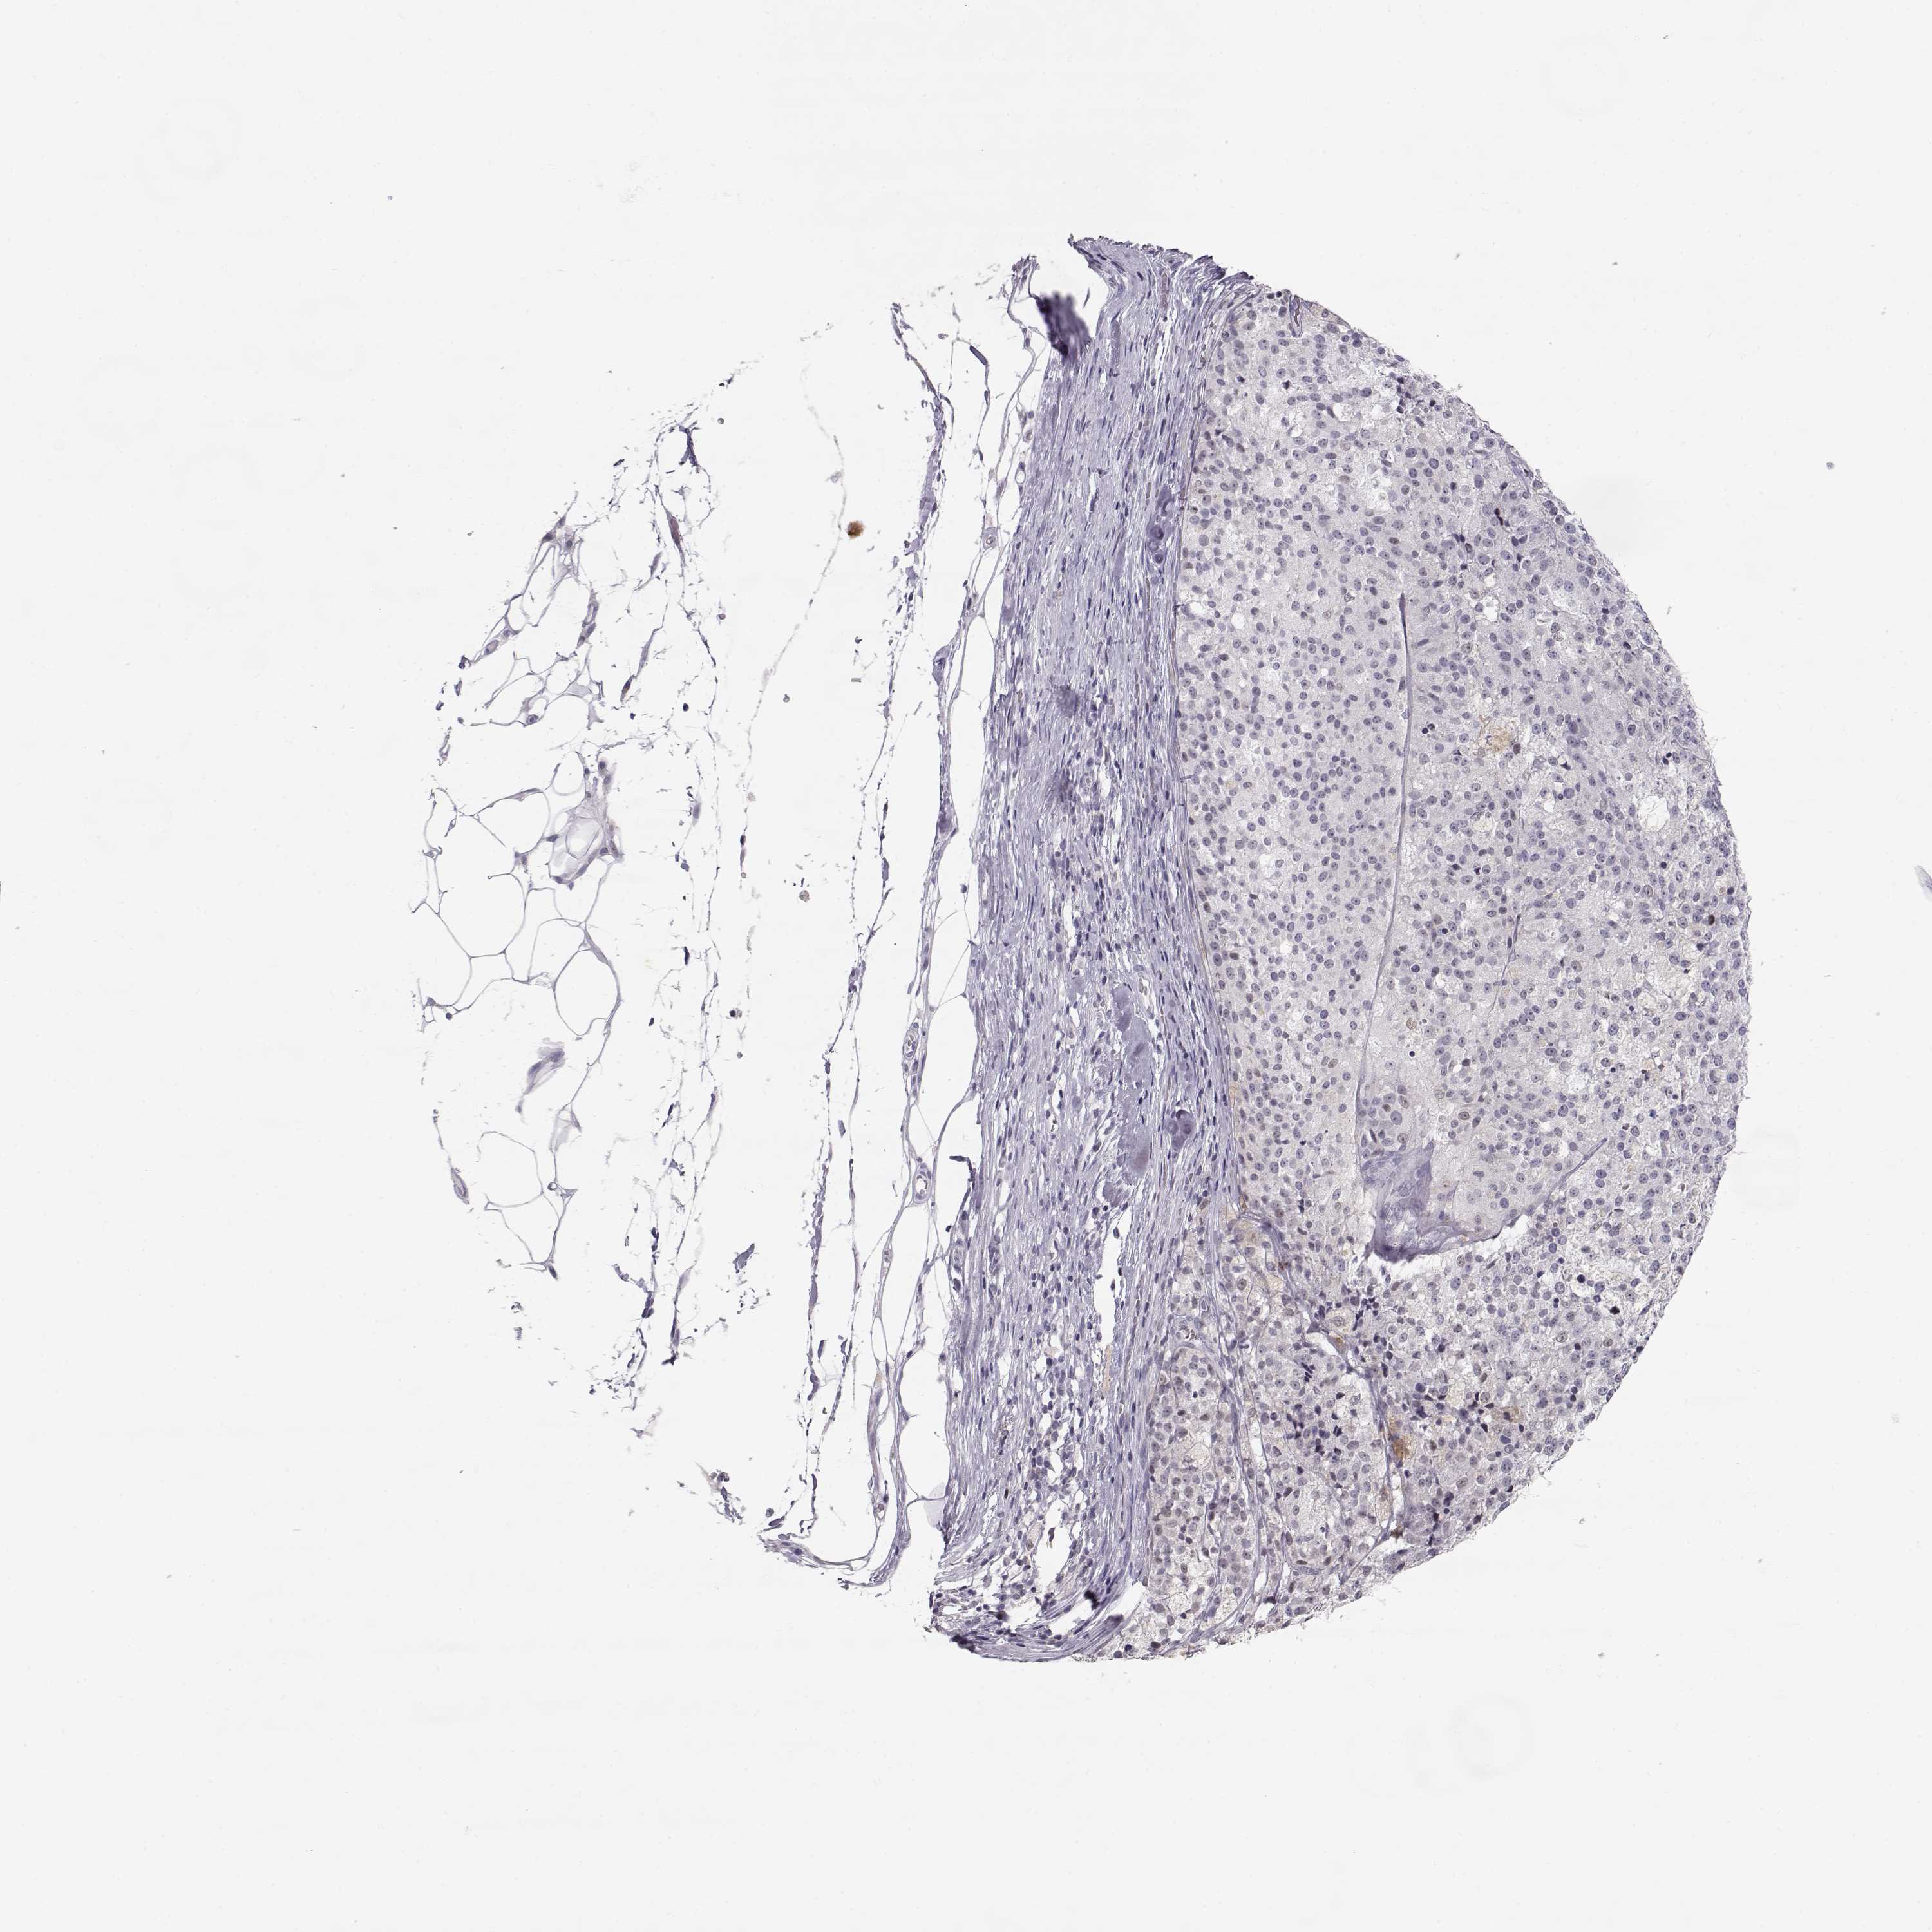

MELANOMA - Protein expressioni

A mouse-over function shows sample information and annotation data. Click on an image to view it in a full screen mode. Samples can be filtered based on level of antibody staining by selecting one or several of the following categories: high, medium, low and not detected. The assay and annotation is described here.

Note that samples used for immunohistochemistry by the Human Protein Atlas do not correspond to samples in the TCGA dataset.

Antibody stainingi

Antibody staining in the annotated cell types in the current human tissue is reported as not detected, low, medium, or high, based on conventional immunohistochemistry profiling in selected tissues. This score is based on the combination of the staining intensity and fraction of stained cells.

Each image is clickable and will lead to virtual microscopy that enables deeper exploration of all samples and also displays staining intensity scores, fraction scores and subcellular localization as well as patient and tissue information for each sample.

Antibody HPA062092

Staining

High

Medium

Low

Not detected

Intensity

Strong

Moderate

Weak

Negative

Quantity

>75%

75%-25%

<25%

None

Location

Nuclear

Cytoplasmic/membranous

Cytoplasmic/membranous,nuclear

Malignant melanoma, NOS

Malignant melanoma, Metastatic site